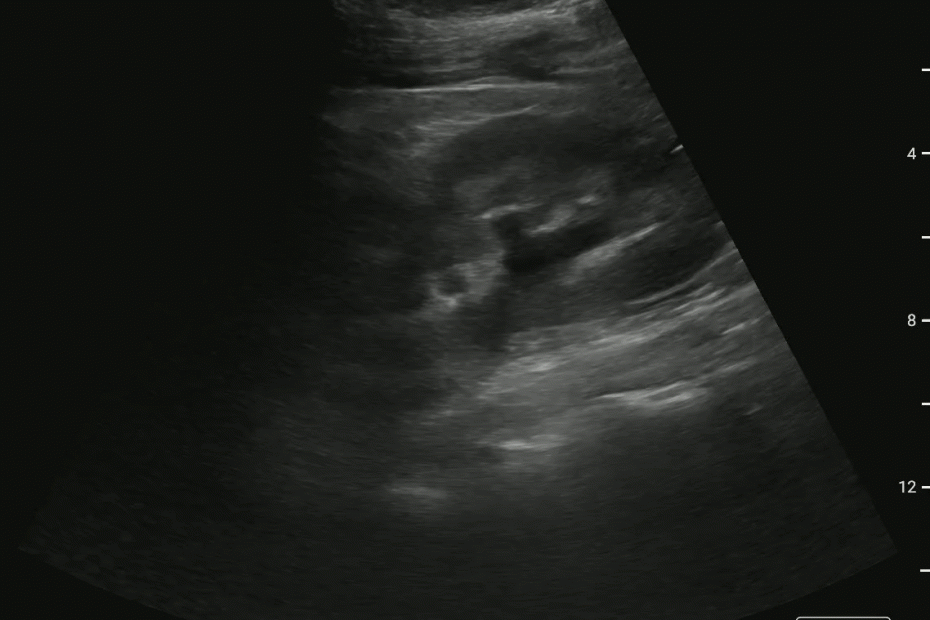

Prox Ureteral Stone, Sponge Kidney